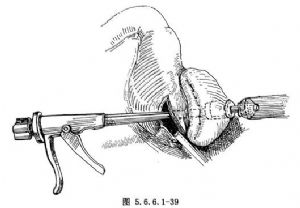

(5)在食管荷包缝线下方3~3.5cm之食管前壁顺其纵轴作一长3cm纵形切口,切开食管前壁并显露管腔,经此切口将抵钉座向上插入食管腔内;结扎荷包线后再用原线反扎一道,或另用7号丝线与荷包线重叠结扎,使食管残端固定于抵钉座的中心杆上(图5.6.6.1-39)。

(6)于食管荷包缝线及结扎线之下0.5cm切除肿瘤食管(图5.6.6.1-39),近侧断端用乙醇消毒。在切除肿瘤食管时,所留食管近侧断端不能过长,否则吻合时形成食管近侧断端外翻,嵌顿于被吻合的两层组织之间,影响订合和吻合口之愈合;但如过短,食管近侧断端容易从中心杆上滑脱,或造成订合不全。